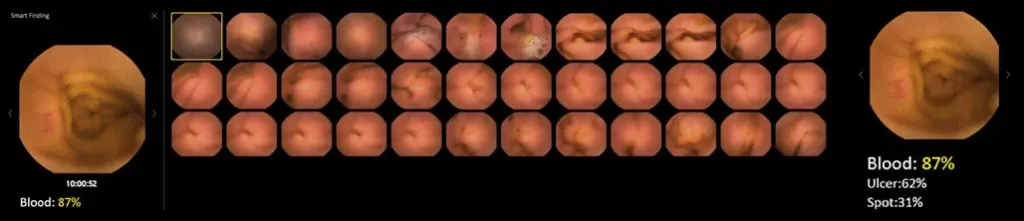

Vue Smart™

Wykorzystując zastrzeżone algorytmy sztucznej inteligencji, SmartScan przetwarza surowe pliki obrazów, usuwając do 90% nadmiarowości, identyfikując i oznaczając aż 16 rodzajów nieprawidłowości.

Tryb czytania SmartView odtwarza tylko obrazy pobrane przez Smartscan, pomagając nam szybciej poruszać się po całym filmie. Dzięki temu możemy przyspieszyć proces diagnostyczny.

Tryb czytania SmartView odtwarza tylko obrazy pobrane przez Smartscan, pomagając nam szybciej poruszać się po całym filmie. Dzięki temu możemy przyspieszyć proces diagnostyczny.